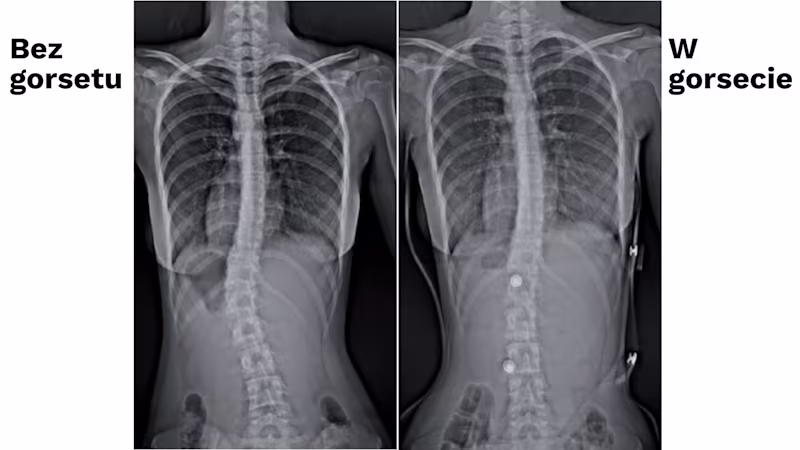

Zalecamy regularne wizyty kontrolne u ortotyka Ottobock w celu oceny postępów leczenia i ewentualnej korekcji, która zazwyczaj wiąże się z niewielkimi modyfikacjami konstrukcyjnymi lub zmianą pelot korygujących. Po 6-8 tygodniach od wykonania zaopatrzenia należy rozważyć wykonanie badania radiologicznego w gorsecie, co pozwoli ocenić efekty terapii. Gorsety ortopedyczne wykonywane w Ottobock są dostosowane do indywidualnych potrzeb pacjenta. Oznacza to, że niezbędne jest pobranie miary, która będzie podstawą do wykonania pozytywu. Obecnie stosuje się następujące sposoby wykonywania zaopatrzenia (pobranie miary):